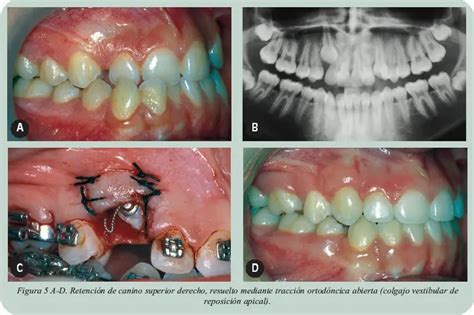

Cuando la cirugía es necesaria se descubre la corona del canino con reposición apical del colgajo cuando se encuentra por vestibular o simplemente liberando la corona del hueso y mucosa cuando está por palatino, respetando siempre la unión cemento-esmalte.

En la radiografía panorámica observamos canino superior derecho retenido, segundos molares permanentes superiores e inferiores en vía de erupción y terceros molares inferiores incluidos.

Posteriormente se remitió a la paciente a cirugía para el abordaje quirúrgico del canino superior derecho y colocación del botón para iniciar la tracción del mismo.

Se distalizaron caninos con cadena elástica, se retiró el botón y se colocó brackets de canino superior derecho y se continúa nivelación con arcos .014” Niti, .016” Niti .016 acero inoxidable (SS).

En publicaciones previas, se ha propuesto un abordaje combinado quirúrgico (colgajo) y ortodóntico (tracción directa hacia el centro del reborde) con el propósito de simular un patrón fisiológico de erupción del canino.

Esta técnica está dirigida a permitir que el canino reposicionado quede rodeado por una cantidad fisiológica de encía al final del tratamiento ortodóncico.